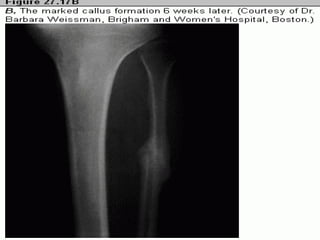

In this region of a recent fracture, callus is seen forming at

the broken ends of bony trabeculae that extend to the

center from the left and top.

This is irregular new bone, or woven bone, which is forming

in the region of a fracture. Osteoblasts are seen lining the

irregular trabeculae, and there is an osteoclast near the

center.

In this regionof a recent fracture, callus is seen forming at the broken ends of bony trabeculae that extend to the center from the left and top.

This is irregularnew bone, or woven bone, which is forming in the region of a fracture. Osteoblasts are seen lining the irregular trabeculae, and there is an osteoclast near the center.